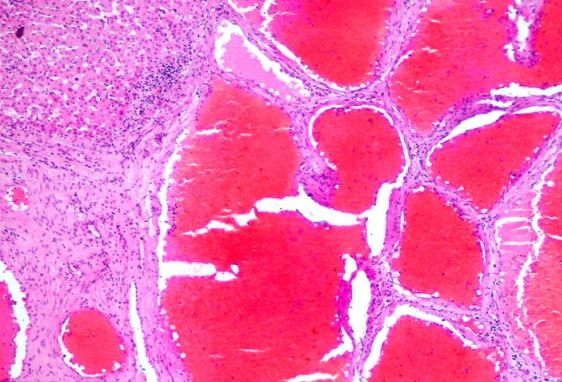

Stomatoloog leidis 23 a mehe suu läbivaatusel kurgunibu piirkonnast kasvaja (vt pilt ülal). Kasvaja ei põhjustanud muid kaebusi kui vähest neelamishäiret. See eemaldati ja saadeti patohistoloogiliseks uuringuks. Milline järgnevatest fotodest sobib antud diagnooisga?